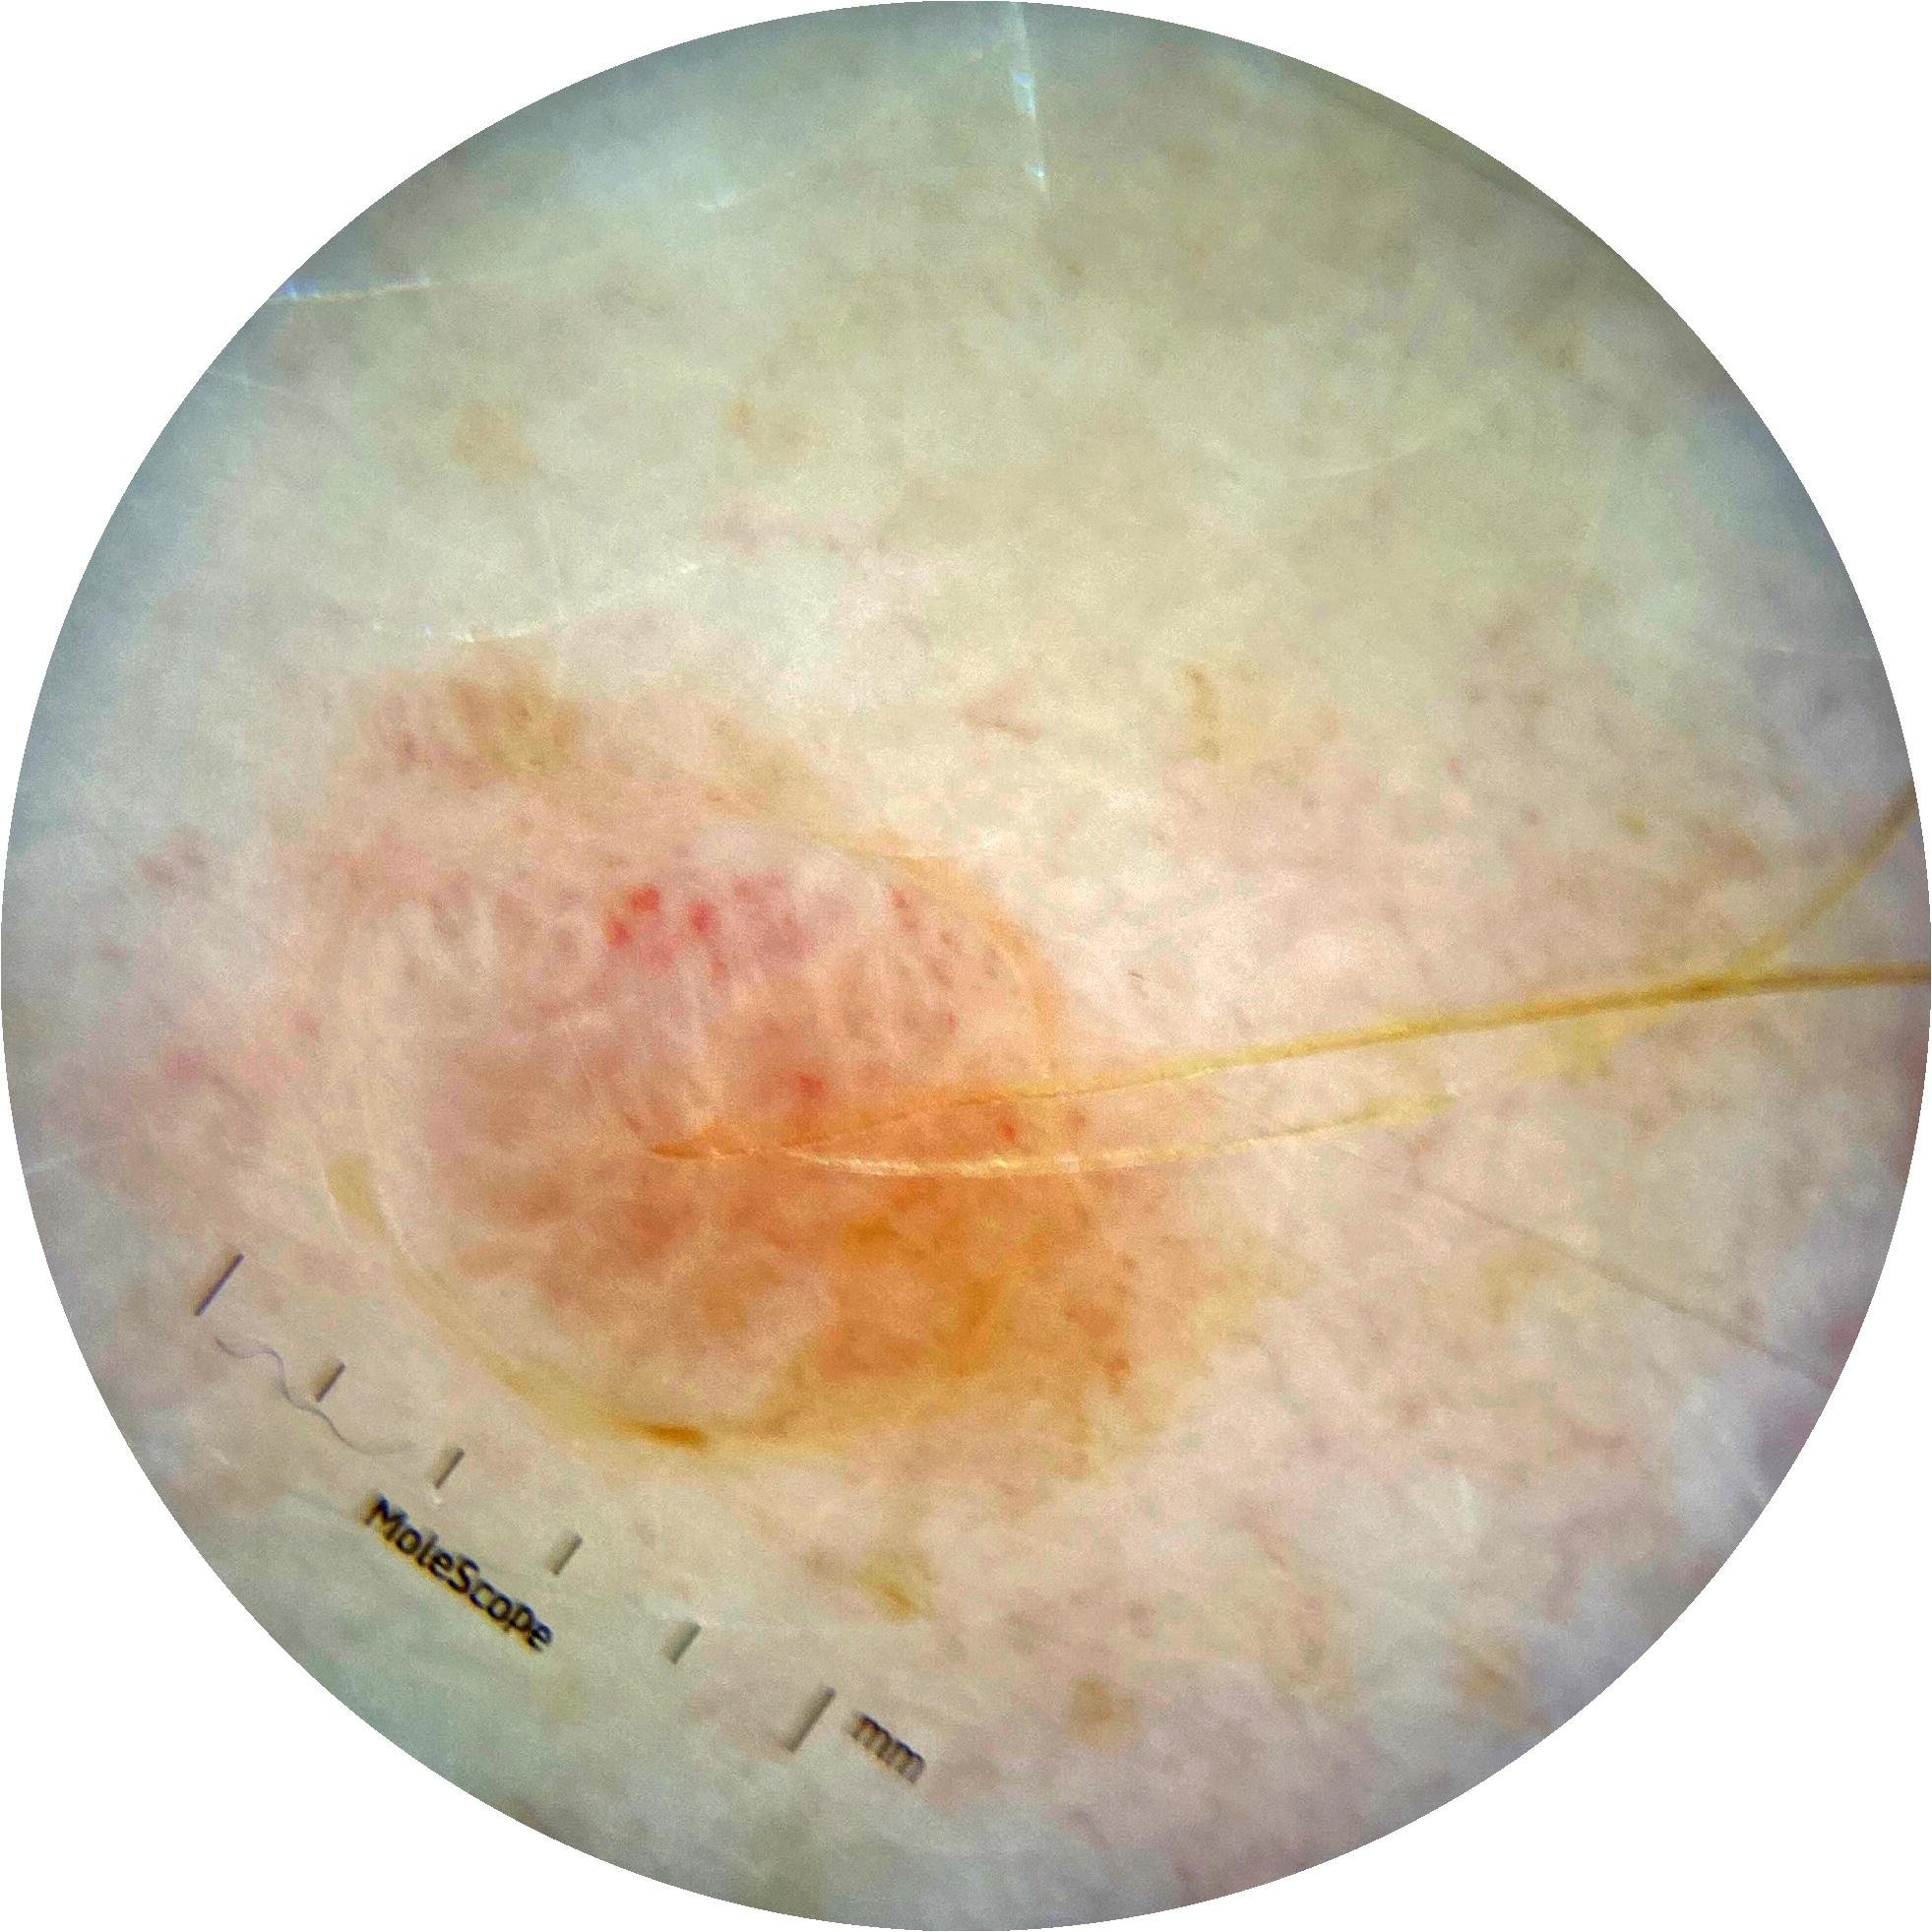

ISIC_7193897

IP_3751325

IL_3780211

Clinical

Field Value

acquisition_day 251

age_approx 65

anatom_site_1 Lower extremity

anatom_site_general lower extremity

concomitant_biopsy False

diagnosis_1 Benign

diagnosis_confirm_type single image expert consensus

family_hx_mm False

image_manipulation instrument only

image_type dermoscopic

lesion_id IL_3780211

patient_id IP_3751325

personal_hx_mm True

sex female